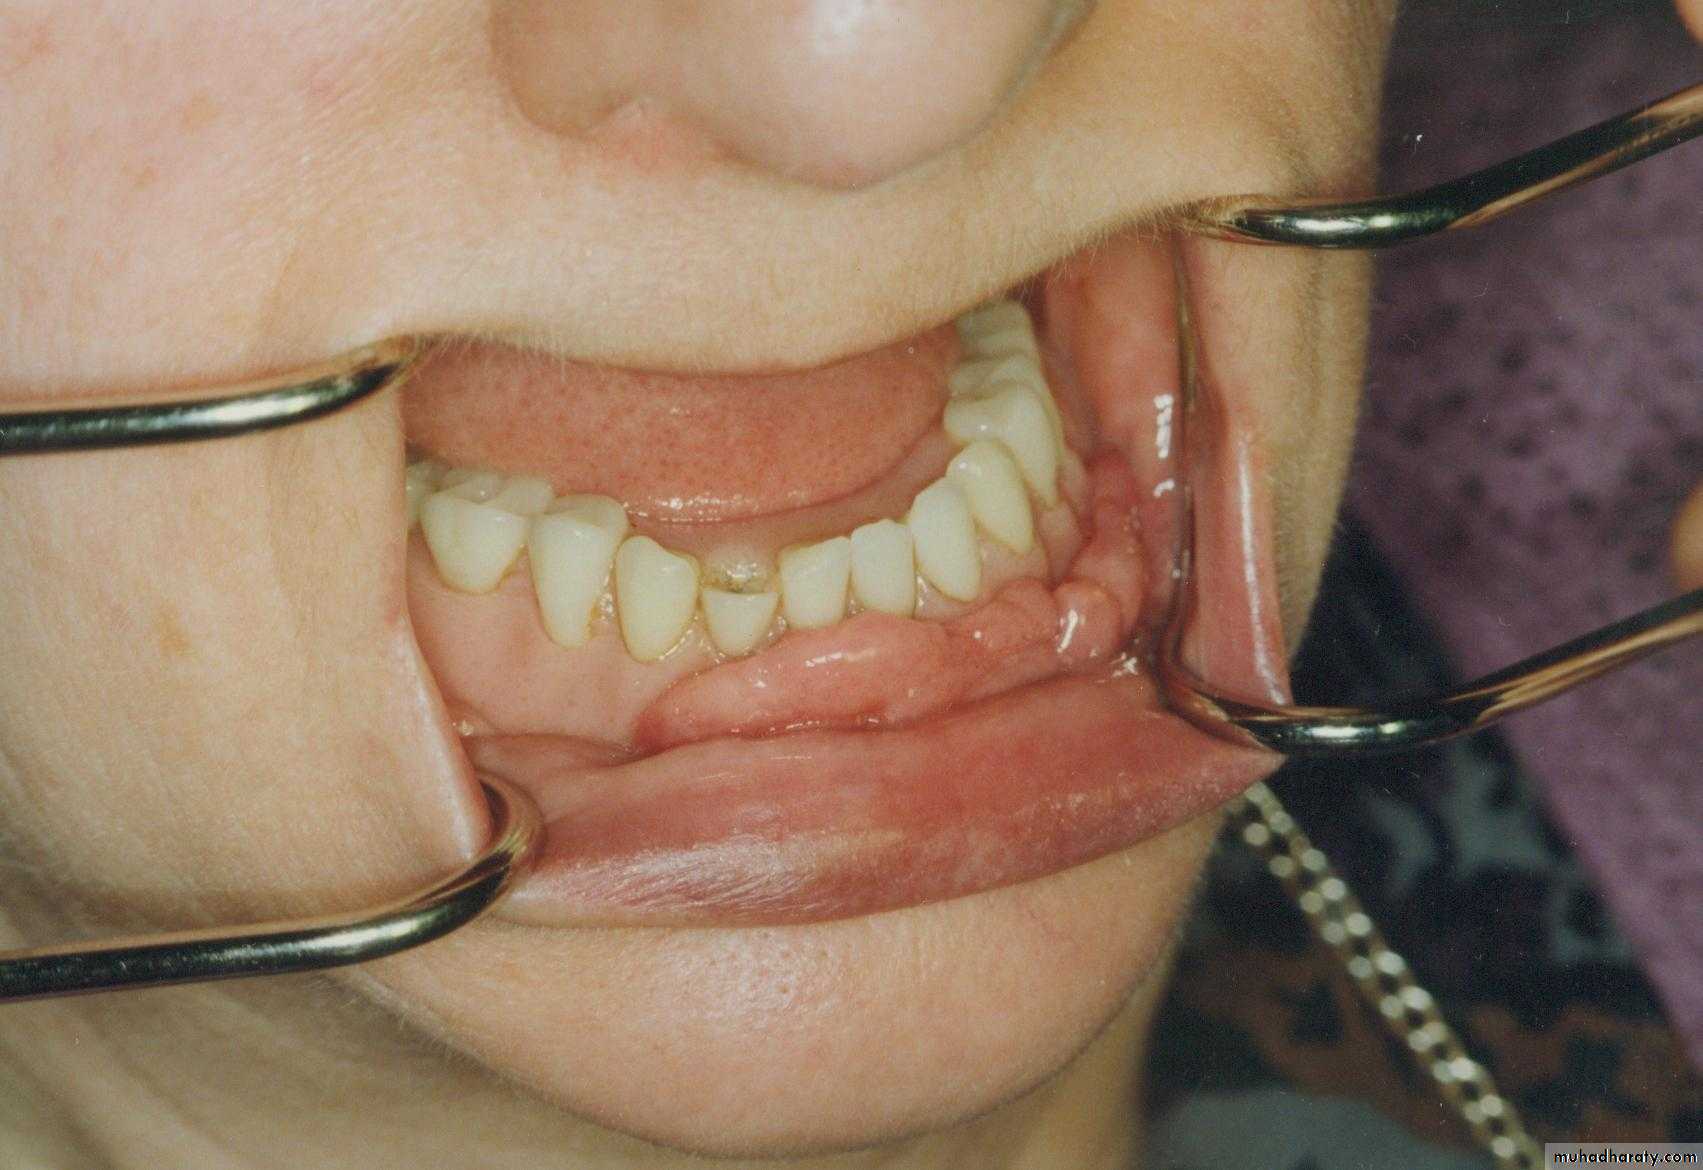

Preprosthetic Surgeryc. Gingivoplasty or frenectomy for flabby ridge tissue or high frena that interfere with support or retention

Gingivoplasty

c. Frenectomy1